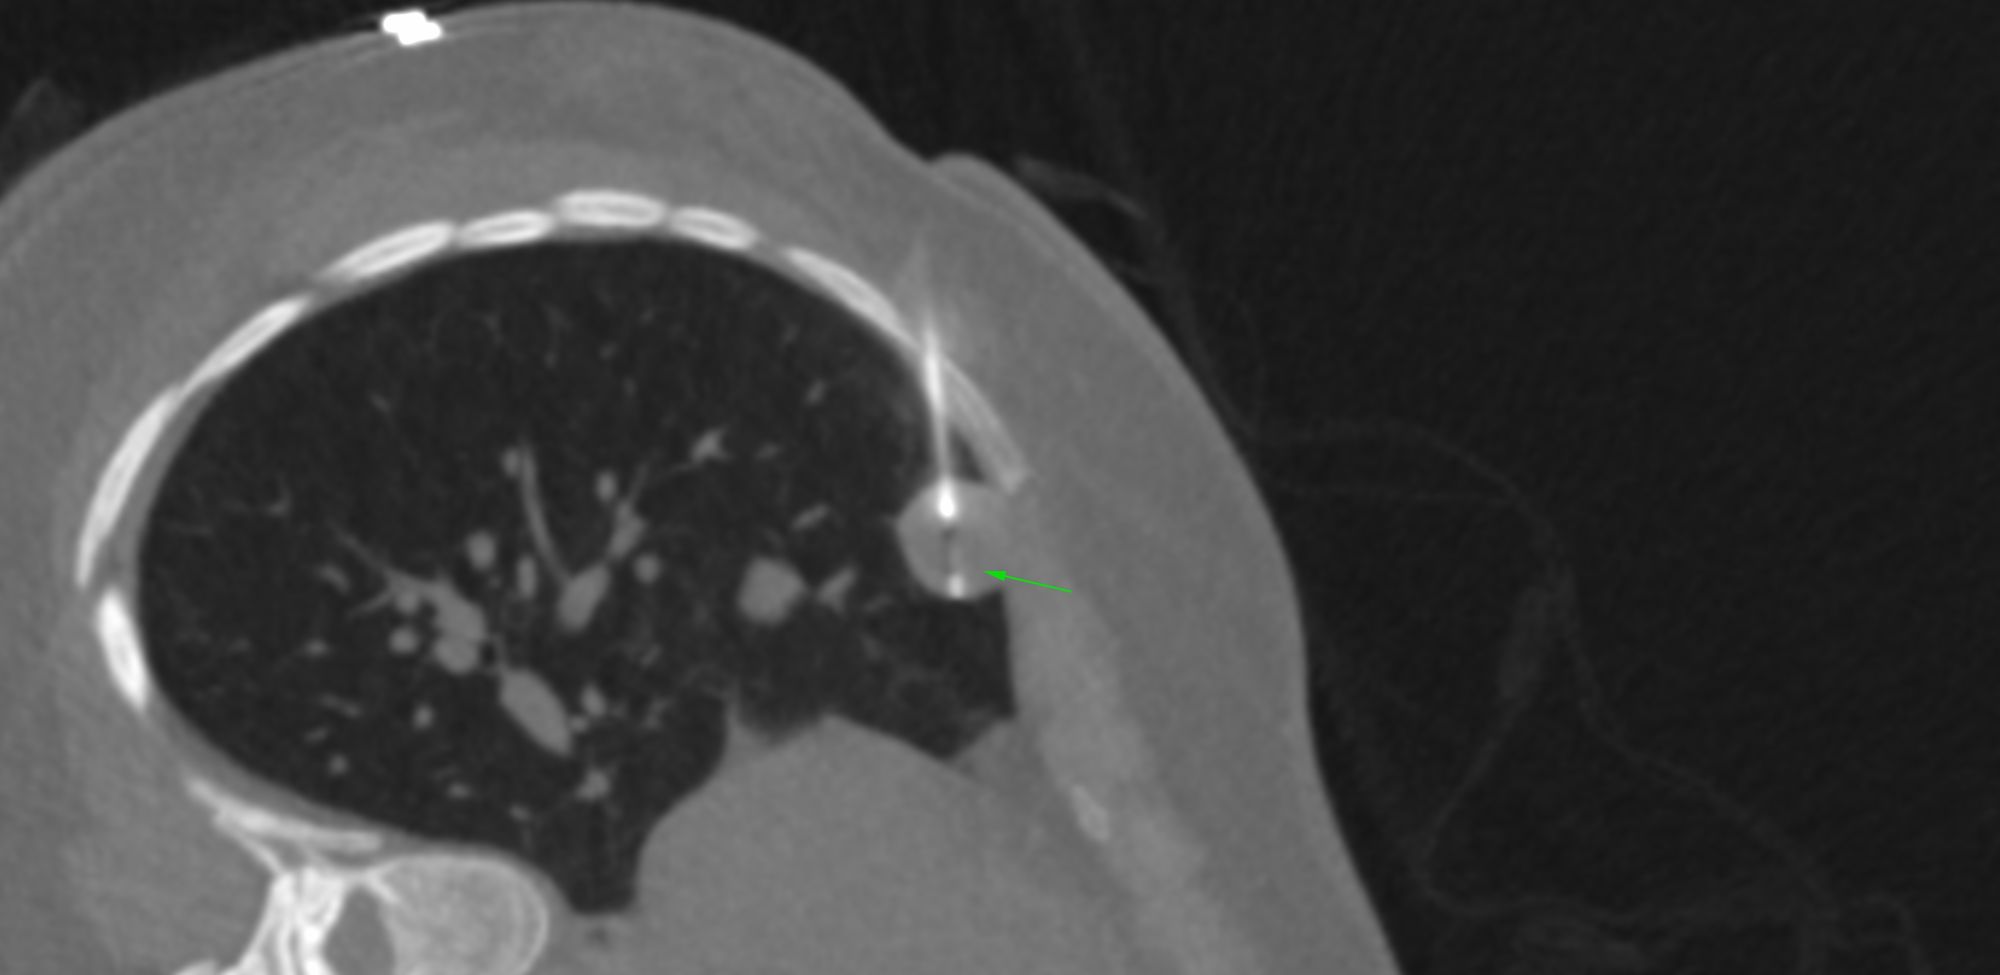

Case 39: Transscapular Biopsy of a Loculated Pleural Collection

Bhavin Jankharia - 02 June 2021